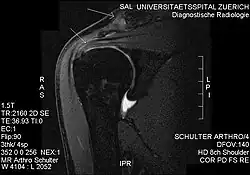

Der Begriff wird vorwiegend für die Schulter verwendet (subacromiales Impingement). Degeneration oder Verletzung der Rotatorenmanschette (Rotatorenmanschettenruptur) sind hier die häufigste Ursache. Betroffene Patienten können aufgrund der zunehmenden Einklemmung der Supraspinatussehne den Arm kaum noch über Schulterhöhe heben. Das eigentliche Impingement entsteht subacromial, also unterhalb des Schultereckgelenkes, weshalb hier von Subacromialsyndrom (SAS) gesprochen wird.